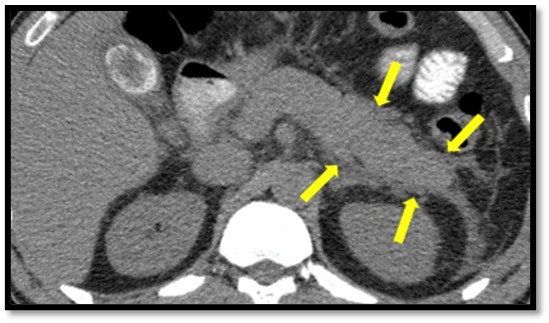

Figure 1: Non-contrast and contrast-enhanced CT scan of the abdomen and pelvis

Transverse section: The pancreas is enlarged with a heterogeneous appearance, showing peripancreatic fat stranding suggestive of inflammation and fluid accumulation. There is associated free fluid in the peripancreatic region, with no areas of necrosis (Yellow arrows).